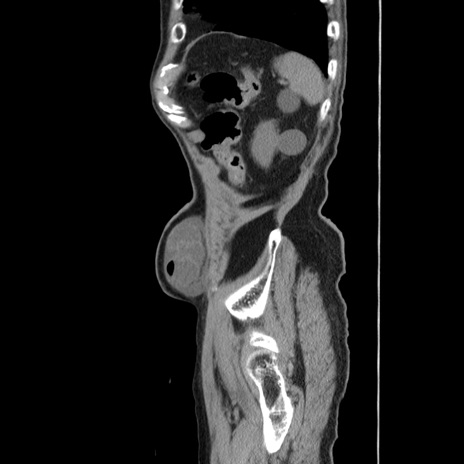

症例24(矢状断像)

【症例】80歳代男性

【主訴】左側腹部痛、嘔吐

【現病歴】本日早朝より左腹部に痛みあり。昼頃嘔吐認めたため、救急要請。

【既往歴】直腸癌(Mile手術)、胆摘

【身体所見】意識清明、BT 35.9℃、BP 221/93mmHg、SpO2 97%(RA) 、腹部:左ストーマ周囲に限局性の腹部膨隆あり。 膨隆部自発痛・圧痛あり・軟。

【データ】WBC 7700、CRP 0.09